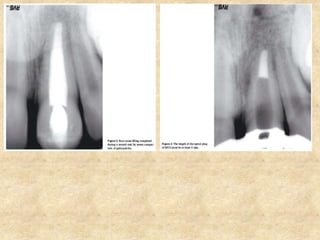

5. Apical plug (Apexification of non vital of immature roots):

• This problem is solved with the use of MTA. An MTA plug of 4mm

thickness placed at the apical region is adequate to form a barrier,

sealing the canal from the periapical area.

• Mixed MTA is placed in the cavity using a large amalgam carrier. The

material is pushed towards the apical foramen with a plugger or paper

points.

• The apical plug should be at least 3 to 4 mm thick and this should be

checked radiographically.

• If the apical plug could not be placed adequately, the entire material is

rinsed from the canal with sterile water and the procedure repeated.

• A moist cotton pellet is placed in the canal and the tooth is temporarily

restored.

• After 3 hours, the remaining canal is obturated with gutta percha and a

permanent restoration is then placed.

Steps involved in apical plug placement